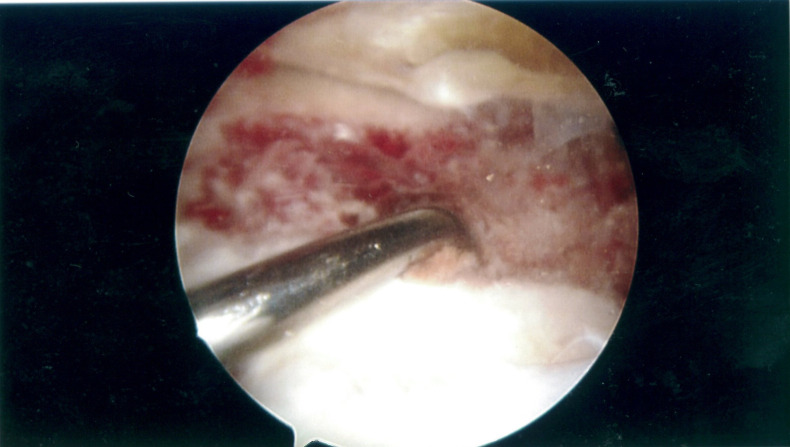

Figure 9.

Arthroscopic view of left knee showing erythematous area at the site of the posterior horn of the lateral meniscus thought to be the source of the haemarthrosis.

Figure 10.

Arthroscopic view of lateral joint compartment post debridement, diathermy and washout.

During arthroscopy, lateral dominant osteoarthritis was observed along with intra-articular blood clots and haemosiderin deposits on the synovium. A small erythematous area was identified at the posterior horn of the lateral meniscus thought to be a thrombosed end of a branch of a peripheral artery supplying the lateral meniscus and therefore the source of the haemarthrosis, as observed in previous literature.1 5 7 8 The lateral meniscus was debrided to stable edges, with the associated erythematous area treated with diathermy to coagulate. The absence of recurrence of haemarthrosis at 1 year post-treatment of the posterior horn of the lateral meniscus further supports the hypothesis that the aetiology of spontaneous haemarthrosis of the knee is from peripheral arterial branches supplying the posterior horn of the lateral meniscus, possibly attributable to a branch of the lateral inferior genicular artery. Furthermore, lateral partial meniscectomy can potentially lead to lateral compartment osteoarthritis and as a potential sequela, spontaneous knee haemarthrosis.